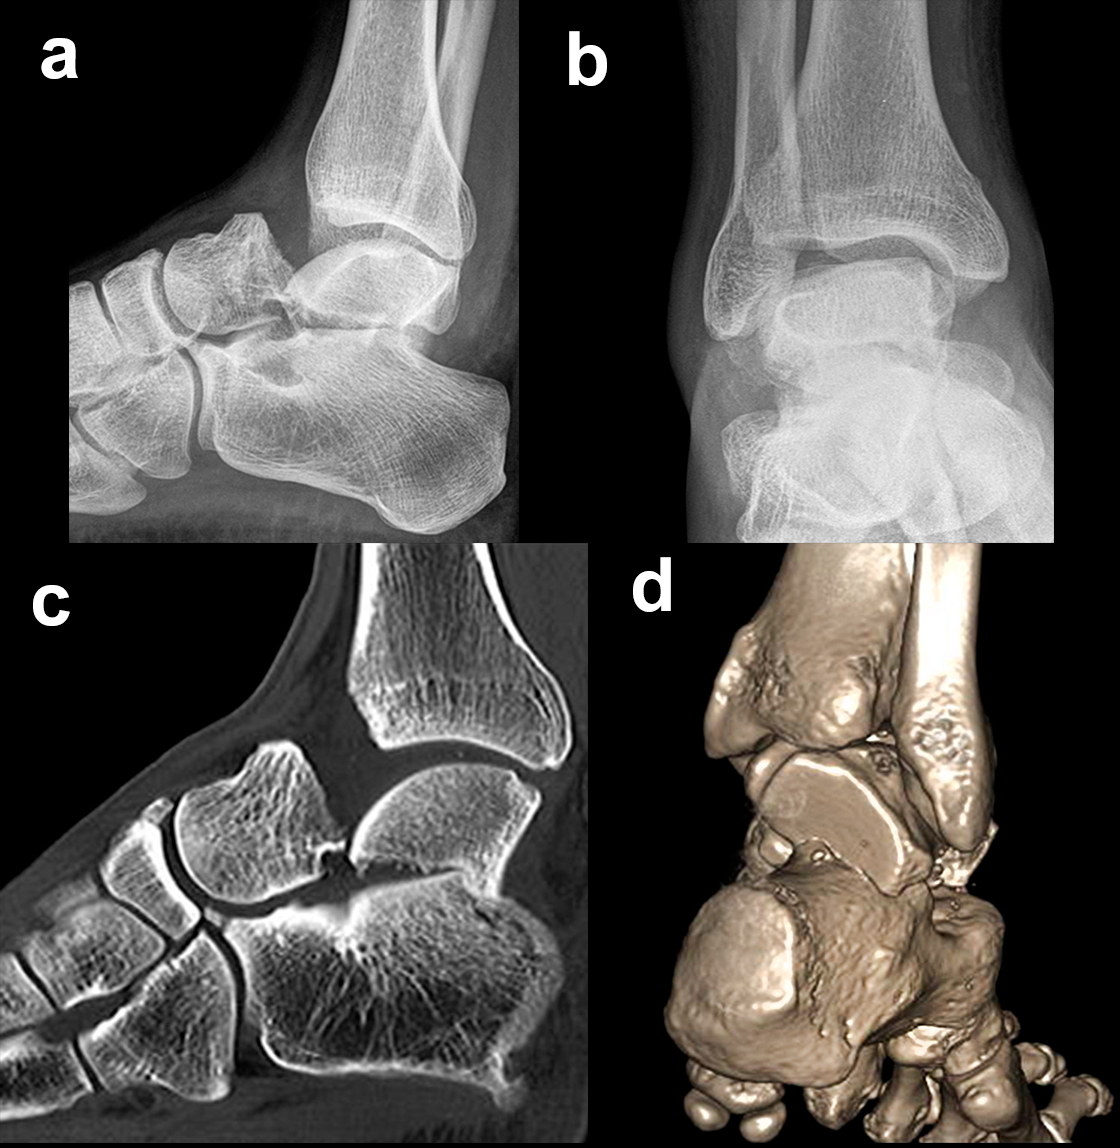

Frakturen des Proc. fibularis tali

Frakturen des Proc. fibularis tali werden im konventionellen Röntgenbild nicht selten übersehen. Sie entstehen häufig nach schweren Distorsionen bzw. im Rahmen subtalarer Luxationen. Eine CT-Kontrolle nach geschlossener Reposition subtalarer Luxationen ist daher obligat (Ab. 15). Der Proc. fibularis tali ist über den anterolateralen Zugang oder schräg verlaufenden Ducroquet-Ollier-Zugang gut zu erreichen. Die subtalare Arthroskopie über anterolaterale und posterolaterale Portale bietet wie bei intraartikulären Kalkaneusfrakturen die Möglichkeit der exakten Kontrolle der geschlossenen Reposition bei einfachen Frakturformen 35. Nach anatomischer Reposition und temporärer Fixierung mittels 1,0 Kirschnerdraht erfolgt die Osteosynthese mittels Kleinfragmentschrauben (2,7 bzw. 3,5 mm), die unterhalb der Knorpel- Knochengrenze eingebracht werden und für eine ausreichende Stabilität sorgen (Abb. 16). Kleinere, nicht anatomisch refixierbare Fragmente, oder Fragmente mit starker Knorpelkontusion werden vorzugsweise exzidiert (Abb. 17). Gleiches gilt für Frakturen des Proc. posterior tali zur Vermeidung einer posttraumatischen Arthrose 23736.